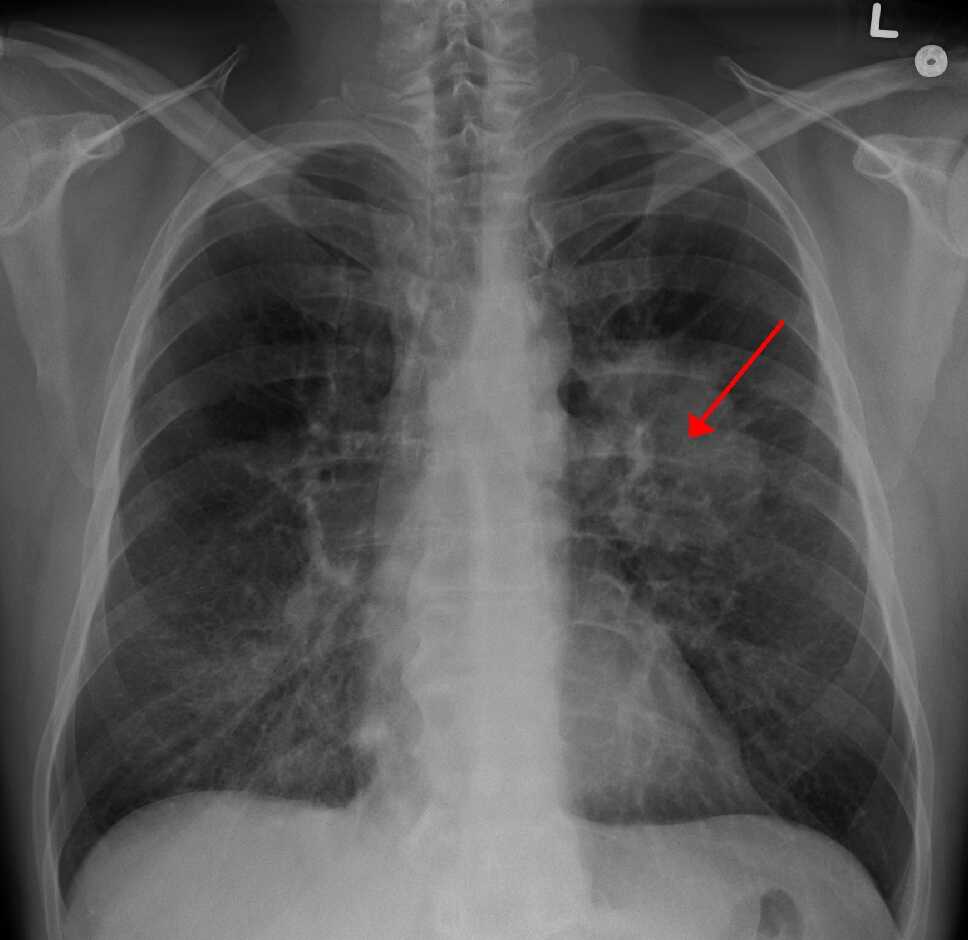

Keterbatasan PET Scan | Sumber: PET CT Scan Service

PET scan tidak digunakan untuk semua kondisi medis. Dokter akan merekomendasikan PET scan jika ada indikasi yang jelas, terutama terkait dengan kondisi yang melibatkan perubahan metabolik sel.

2. Deteksi dan Menentukan Stadium Kanker

Salah satu aplikasi paling vital dari PET scan dibidang onkologi adalah untuk deteksi Kanker, karena biasanya sel kanker menunjukkan metabolisme glukosa yang lebih tinggi dibandingkan jaringan normal, juga menentukan stadium kanker (cancer staging), disamping beberapa manfaat yang lain termasuk menilai respons terapi ad interim (di tengah-tengah pengobatan kanker).

Pemeriksaan ini dapat melihat sejauh mana kanker telah menyebar (metastasis) di tubuh seperti ke kelenjar getah bening atau organ lain di seluruh tubuh.

Dengan akurasi yang tinggi, PET scan memberikan panduan bagi tim medis dalam menyusun rencana pengobatan selanjutnya agar lebih tepat.